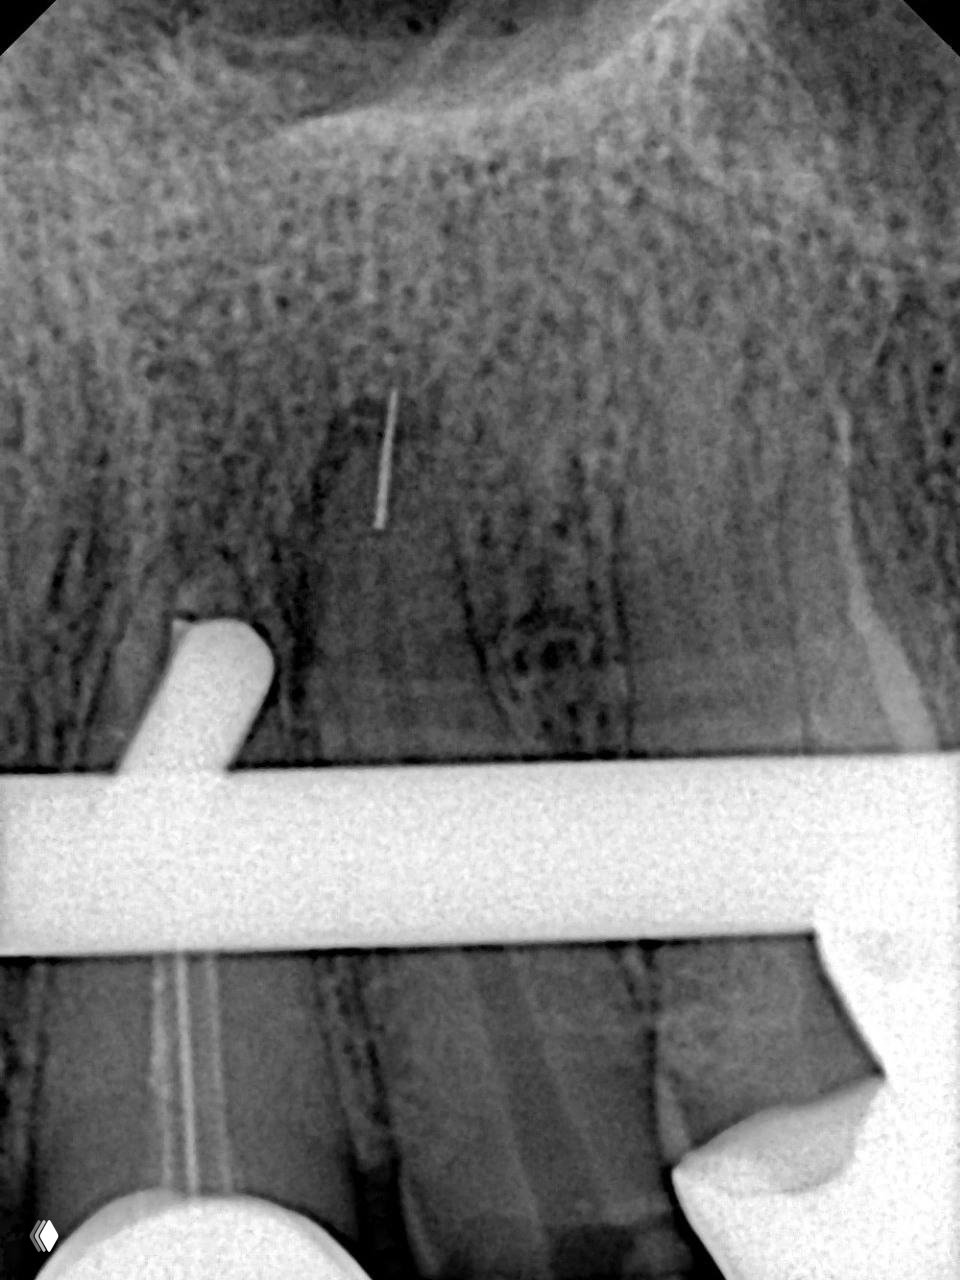

Когда в канале спрятан фрагмент инструмента, тратить время на эксперименты уже не хочется, поэтому расскажу про насадки, к которым я возвращаюсь снова и снова и которые реально выручают в работе🦷

☝️ Первая - это насадка Тераучи E89, E88, E87 от Woodpecker. Кончик всего 0,1 мм, конусность 1, она неплохо гнётся и позволяет сделать очень аккуратную тонкую бороздку вокруг обломка. Для ювелирной работы вещь просто шикарная.